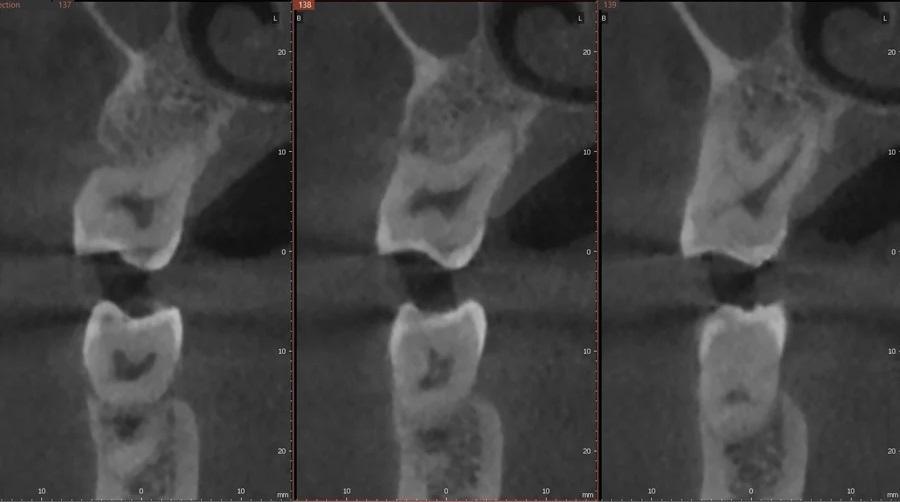

Фото 4. Предоперационное КЛКТ-исследование, указывающее на глубокую фуркацию, распространяющуюся на щечную поверхность небного корня зуба № 2.6, отсутствие щечной компактной пластинки и вестибулярное смещение с лингвальным торком корня.